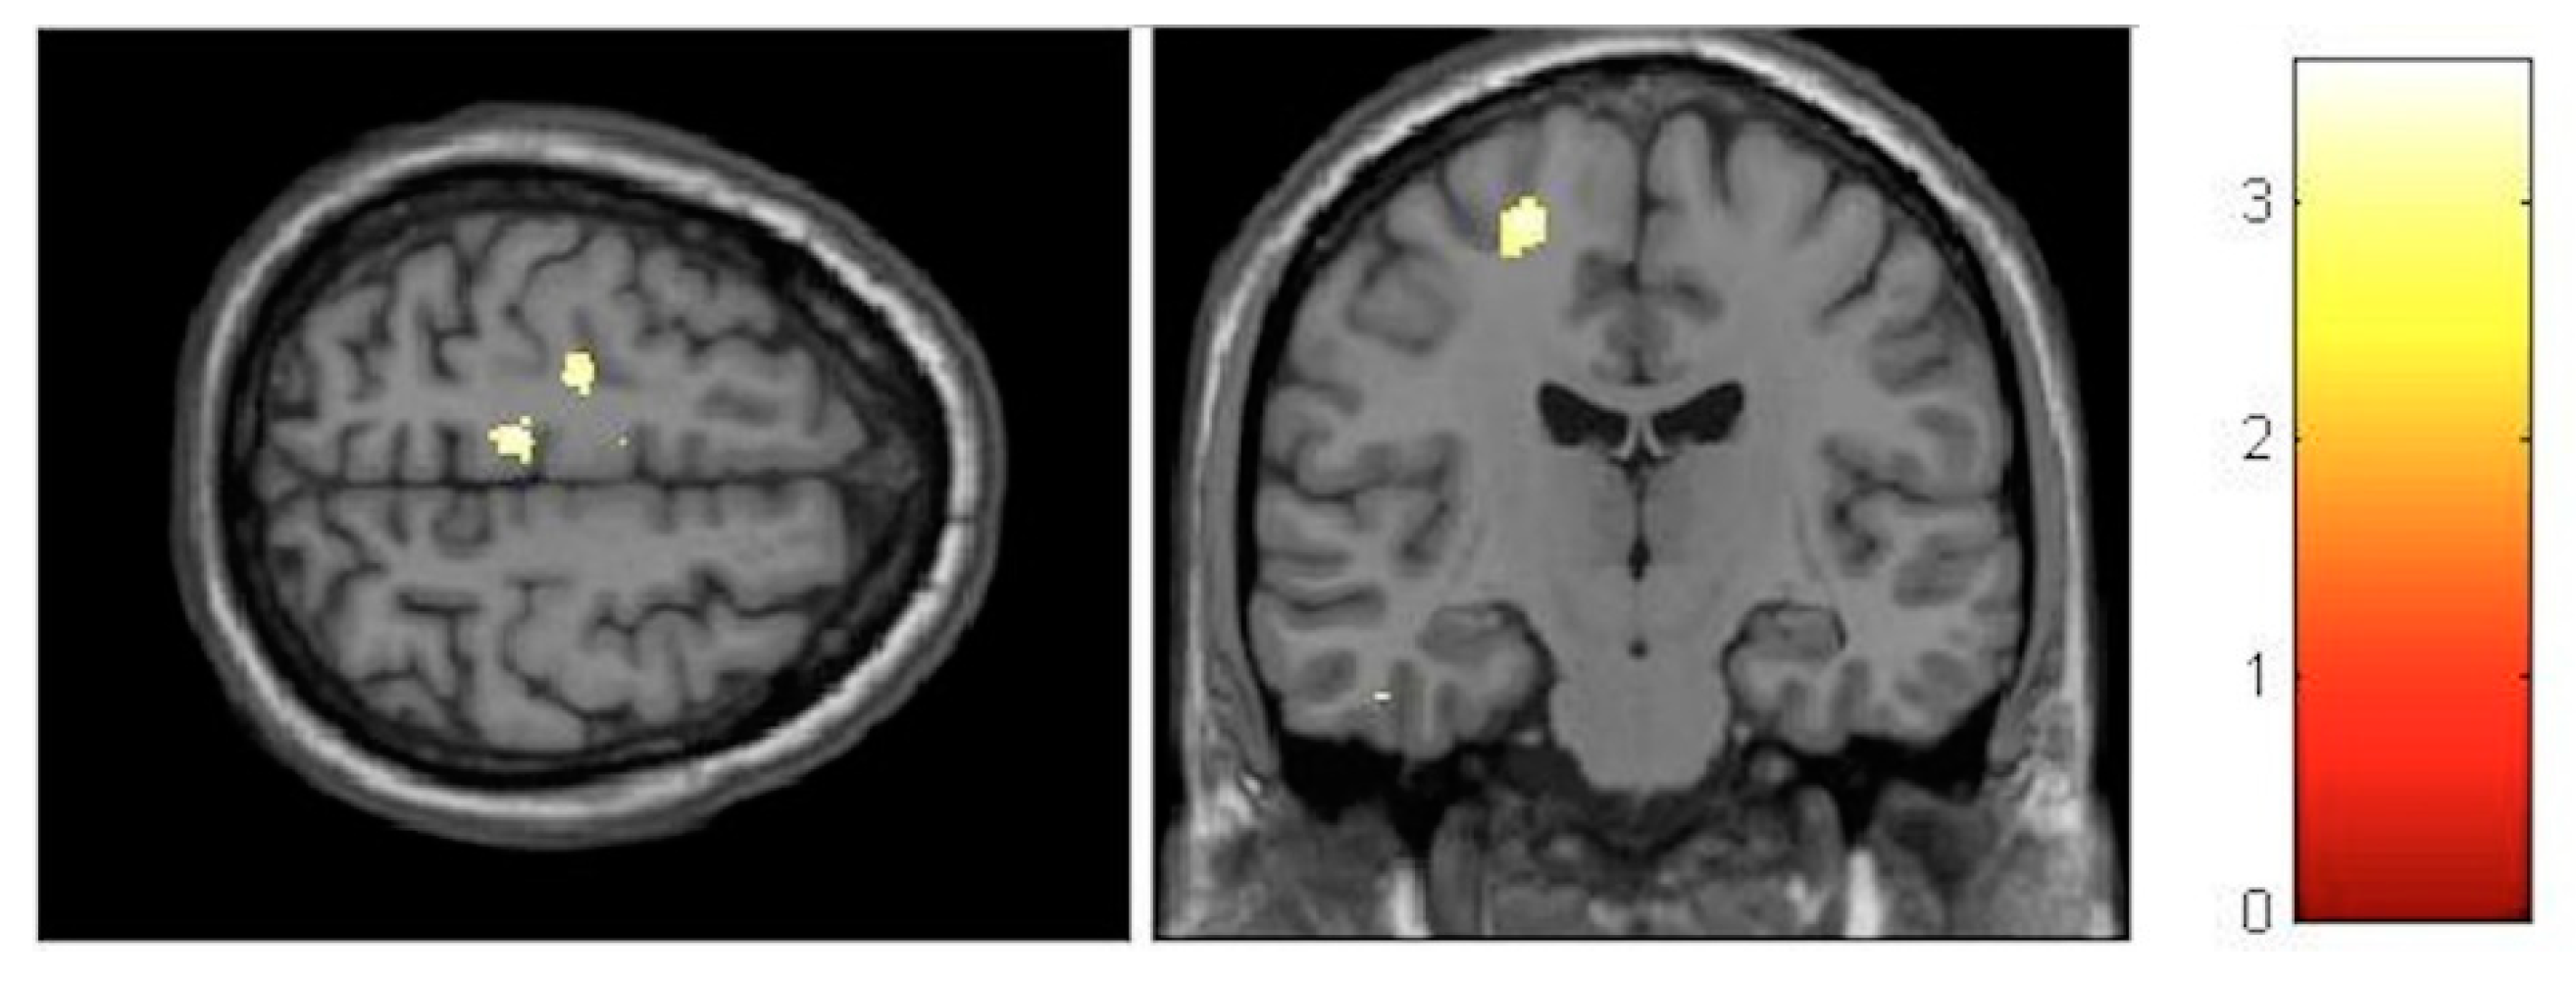

| Effect | Brain Region | Left Hemisphere MNI Coordinates (Cluster Size in Voxels) | T | d | Right Hemisphere MNI Coordinates (Cluster Size in Voxels) | T | d |

|---|---|---|---|---|---|---|---|

| Increment | Sensory-motor | −8, −32, 60 (314) | 5.17 | 0.39 | 11, −29, 60 (1087) | 6.09 | 0.41 |

| Decrement | Hippocampus | 27, −30, −6 (133) 23, −2, −17 (119) | 4.06 4.74 | 0.37 0.38 | |||

| Decrement | Insula | −33, −12, 18 (586) | 5.57 | 0.40 | 33, −17, 17 (797) | 6.17 | 0.41 |

| Decrement | Putamen | −26, 8, 6 (631) | 4.72 | 0.38 | 21, 11, 2 (134) | 4.22 | 0.38 |

| Decrement | Cerebellum | −11, −45, −23 (245) | 3.84 | 0.36 | 11, −65, −23 (224) | 3.99 | 0.37 |